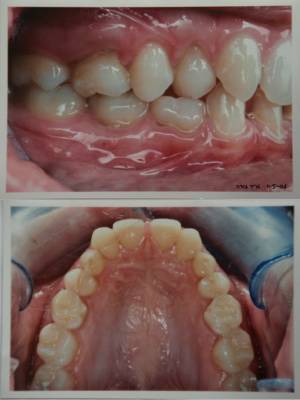

jeune fille de 19 ans avec agenesies:

(18)15,12,22,25(28)

(48)45,42,32,34,35

D’un point de vue orthodontique, , je ne vois personnellement que la zone incisivo-canine inférieure à traiter pour rajouter une incisive et je ne toucherais pas au reste.. Le fait qu’il y ait alors que trois incisives n’a pas d’importance ( il n’y a de toute façon pas la place d’en rajouter deux).

Compte tenu du manque d’os au milieu mandibulaire, je serais tenté d’y déplacer 32 pour en amener.

aux vues de la pano et de la photo intrabuccale,je ne pense pas qu'il y ait assez de place pour un implant (vous confirmez les implantos?),il faudra certainement ouvrir en reculant un peu les 4 et fermant les espaces anterieurs

quant à l'implant inf,je suis comme catrose sceptique sur l'os suffisant en antérieur et encore plus sur le resultat esthetique de 3 incisives face à un diastème ou à des centrales qui vt s'avérer trop grosses si on le comble ou diminue par un artifice prothetique (après avoir reregardé les photos ) ,recherche esthetique qui au départ motive la patiente,ne pas l'oublier

d'un point de vue esthétique il est préférable de distaler les canines et de mésialer les incisives inf....pour les canines...c'est une question de forme...pour les incisives...il est plus facile de gérer la gencive périimplantaire si 1 implant est encadré de 2 dents naturelles qu'entre 2 implants

et au niveau esthetique,on aura des petites canines sup et des petites laterales inf:si je n'ouvre pas un peu tout ca,il me reste maximum 5 mm pour caser les 32 et 42,autant faire comme daniel le propose et placer une seule incisive?

mais pour les canines sup,je trouve que c'est un cas rare ou avec tres peu de maquillage compo (bord incisif),elles s'harmoniseront tres bien en place des laterales:pas de gros bombe cervical,largeur mesio-distale minime,pas de retouche de hauteur coronaire et on repousse l'implant le plus posterieur possible